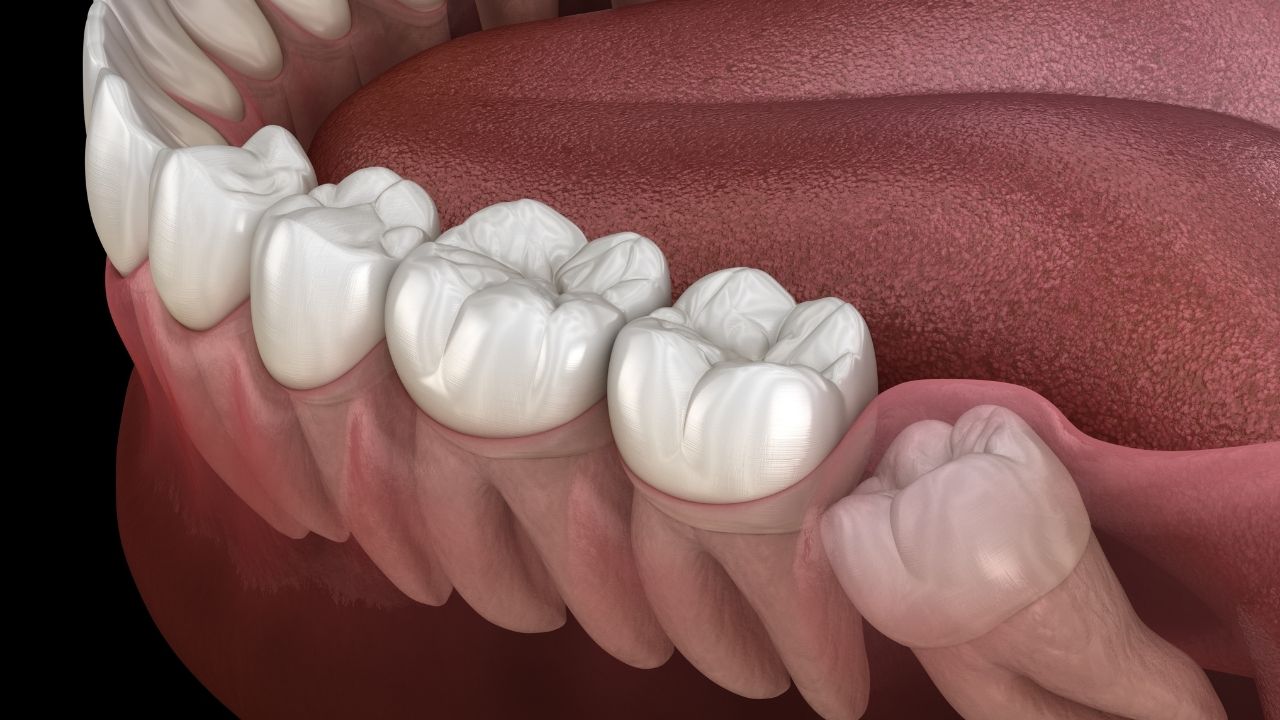

Então o siso pode interferir no alinhamento da arcada dentária?

Sim. Como ele nasce mais tarde, existe a possibilidade de o paciente não ter espaço suficiente na boca para acomodá-lo. Aí, ele pode empurrar os dentes que já estão ali, entortando-os. Mas, lembre-se: cada caso é um caso.